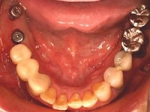

片側2歯欠損 主訴-入れ歯を使ってみたが違和感強くてダメ。固定のものにしたい。術前下顎口腔内(鏡像)

二次オペ時(鏡像)

術後、左下奥2本インプラント(鏡像)